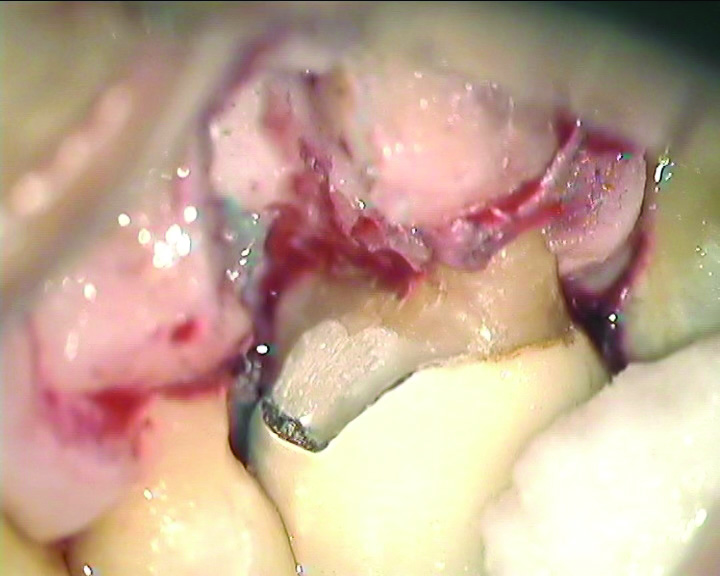

Figure 6, which shows a clinical image of a tooth No. 14 with a mesiobuccal root resection, highlights the desired cantilever contour result. Note that no root stub exists and the cantilever flows smoothly to the retained palatal and distobuccal roots and progresses mesially to a point below the contact space with the adjacent tooth.

During the resection process, directly visualizing the smooth transition to the retained distobuccal and palatal roots is essential and made possible by utilizing an operating microscope. Note that in Figure 6 the underside of the tooth has been restored with a resin-modified glass-ionomer (RMGI) restorative material. The restoration of the underside of the remaining tooth is important to satisfy the objective of a maximally cleansable result. A new restoration to seal the underside of the cantilevered section of the tooth will almost always be needed, except in the few cases where the resection of the root and shaping of the cantilevered section results in the exposure of a perfectly smooth existing restoration with no voids. Most core buildups do not extend into the root canal orifices far enough to satisfy this condition, however, which is why placing a new restoration on the underside of the cantilevered portion should be planned in almost every case. An additional benefit of placing a new restoration that covers much of the cantilevered underside of the tooth is that the underside of the tooth will become more resistant to decay since the restorative material itself cannot directly decay.

Fig 6. A cleansable resected root surface, the root filling, and the root contour will affect the prognosis. Fig 5: Tooth No. 19 at 1-year post-treatment with a remaining stub of the mesial root following root resection; note a subsequent larger-than-expected crestal bone loss defect below the cantilevered portion of the tooth. Incomplete resection and lack of proper contour toward the mesial contact has created a plaque trap and subsequent unstable periodontal status. This problem can be avoided with a more aggressive resection to ensure a cleansable situation. Fig 6: Clinical image of tooth No. 14 with a resected mesiobuccal root and RMGI restoration of the underside of the tooth. The resultant contour has no lips or ridges and has a smooth transition to the mesial contact space; there is also a smooth transition to the remaining distobuccal and palatal roots, creating a cleansable situation. Fig 7: Tooth No. 18 immediately following resection of the mesial root demonstrates a contoured mesial surface that smoothly blends to the mesial contact region. The underside of the cantilevered portion of the tooth is restored with a RMGI restoration, and the socket is grafted with an allograft.

Fig 8: Tooth No. 30 with a resected mesial root and restoration of the underside with a RMGI restoration at 5 years post-treatment is displaying the expected healing pattern of the crestal bone following grafting of the socket. The proper resection and contouring permits adequate maintenance and resultant stability of the tooth.